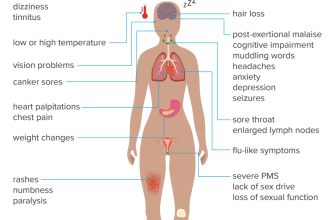

Symptom Database

Learning disabilities are a common issue that affects

Lethargy, also known as fatigue or tiredness, is a